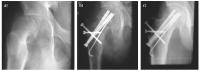

Abbildung 10a-c: Röntgenbild bei ECF, 13 A, männlich. a) Der nach caudal abgerutschte Hüftkopf ist deutlich sichtbar. b) Derselbe Patient nach Schenkelhalsosteotomie

und Osteosynthese. c) Derselbe Patient 1 Jahr postoperativ.